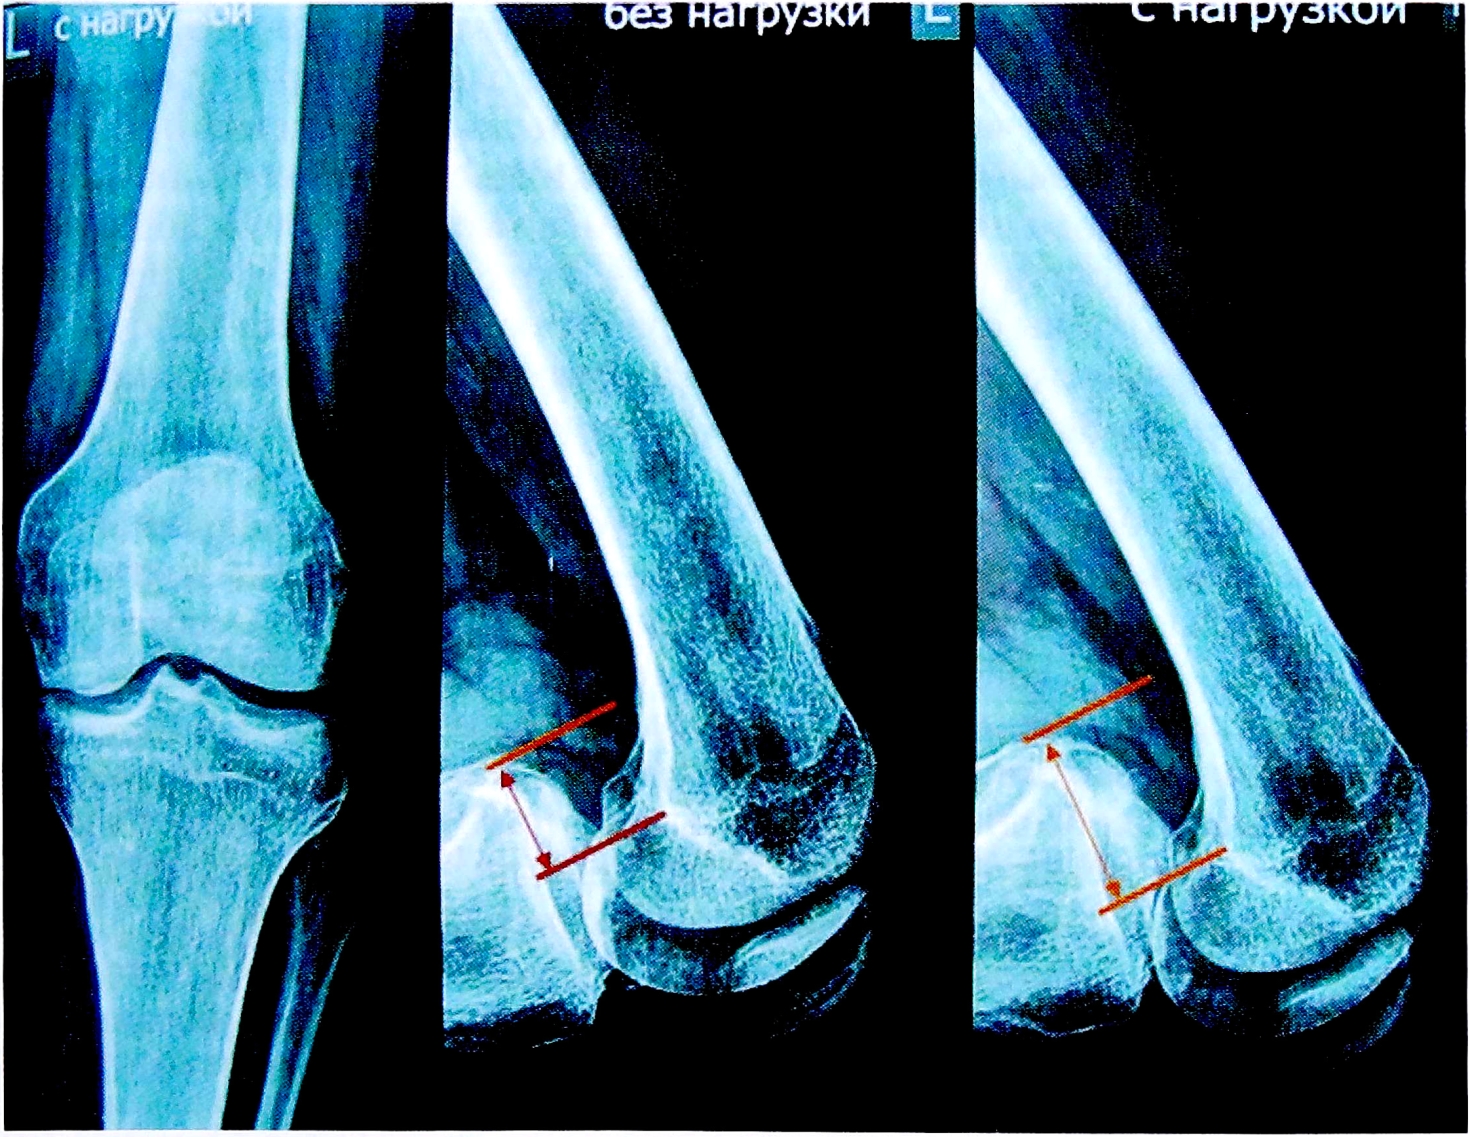

Перед операцией всем пациентам были выполнены МРТ коленного сустава (рис. 1) и рентгенография под нагрузкой (рис. 2). Результаты клинического осмотра, рентгенологических и MPT-исследований фиксировались согласно протоколу IKDC 2000. Для функциональной оценки коленного сустава были использованы опросники IKDC и Lisholm-Gillqist. Болевой синдром оценивался по визуальной аналоговой шкале (VAS).

Рис. 2. Рентгенография коленного сустава с нагрузкой для оценки степени заднего смещения голени.

Fig. 2. Functional X-ray to masure knee posterior instability.